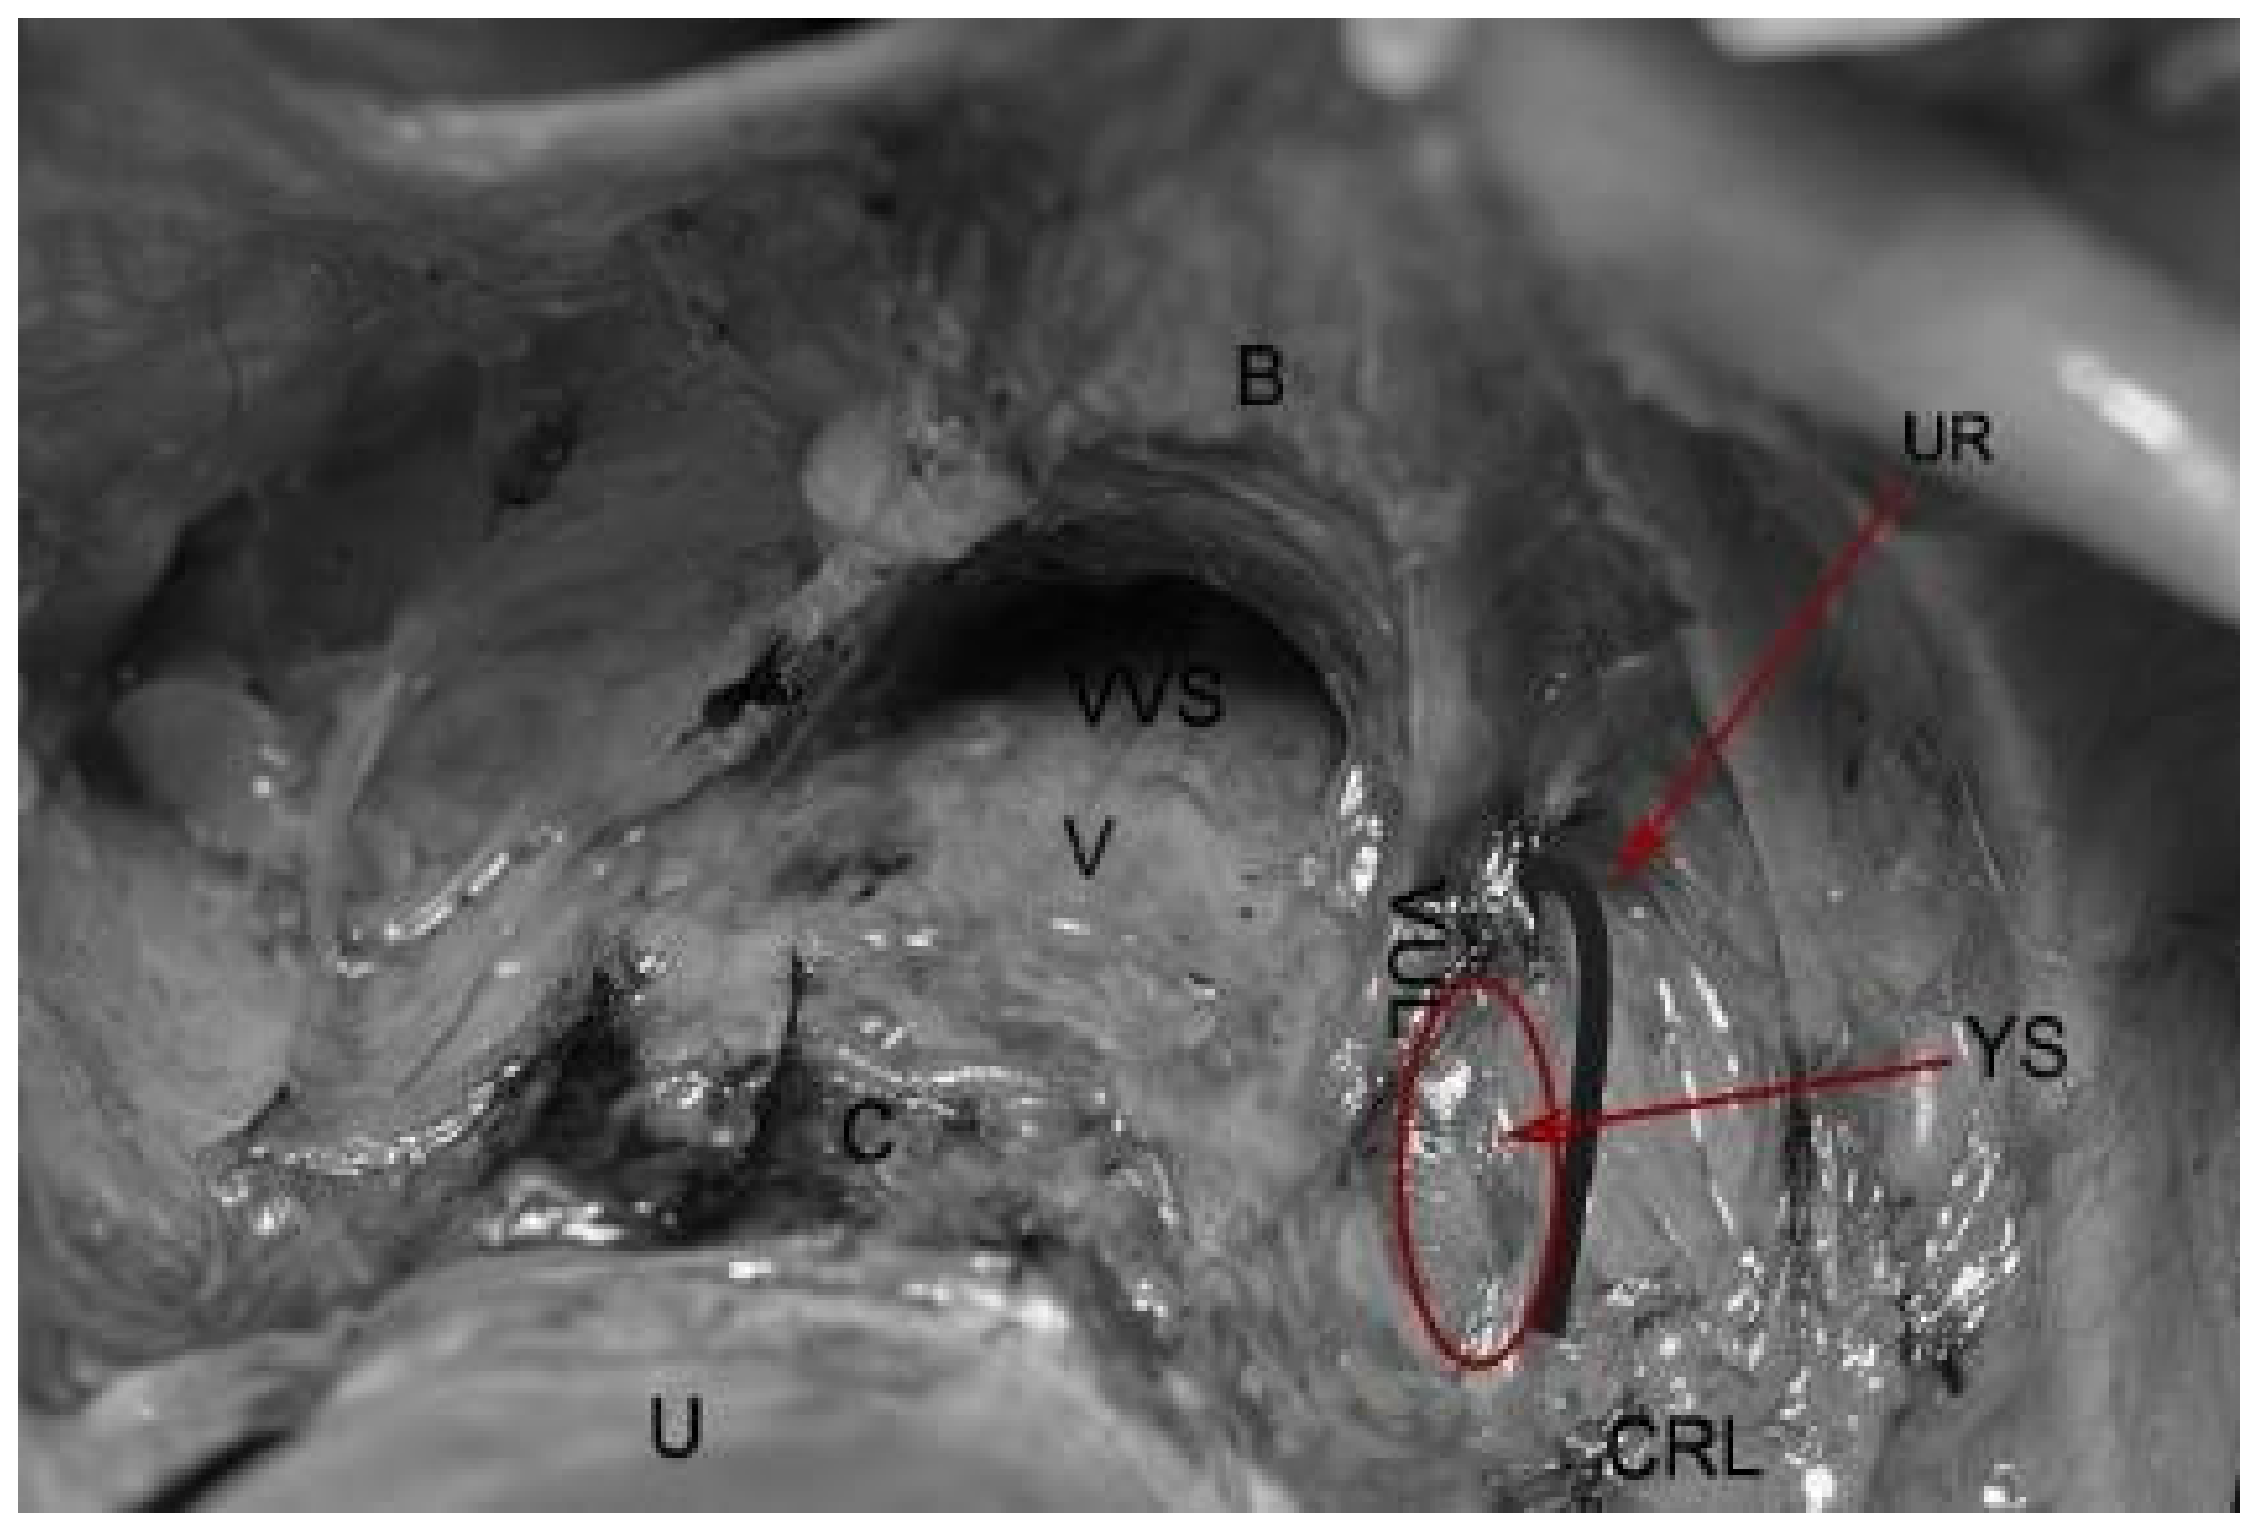

The Yabuki space, also called the fourth place, was first described in 2000 by Yoshihiko Yabuki. It is located between the cranial portion of the vesicouterine ligament and the ureter. The Yabuki space is dissected during nerve-sparing surgery as it contains the pelvic splanchnic nerves on the way for bladder innervation (Figure 9).

The Yabuki space is exposed after dissection of the cranial portion of the vesico-uterine ligament. With the ureter emerging as a target, the fourth space is exposed by dissection and coagulation. Dissection proceeds to the vesicoureteral junction [23,30]. Later in 2005, Yabuki reported the same space as Okabayashi’s paravaginal space [3]. Liang et al. concluded that the Yabuki space should be located between the lateral side of the vagina and the caudal portion of the vesico-cervical ligament [30]. Nerve-sparing techniques in oncologic pelvic procedures are based on anatomical landmarks—four spaces (medial paravesical, Okabayashi, Latzko, Yabuki spaces) and four structures (the ureter, LLR, MRA, and the deep uterine vein) [1,21].

Figure 9. Yabuki space. U—uterus, C—cervix, V—vagina; VVS—vesicovaginal space; B—bladder; VUL—cranial portion of vesico-uterine ligament; UR—ureter; CRL—cardinal ligament; YS—Yabuki space.